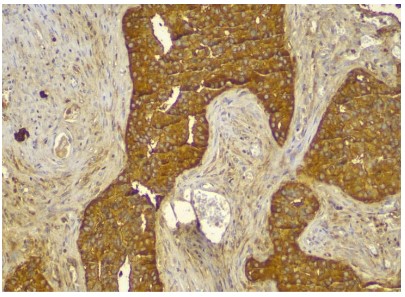

The gross cystic mass measures 10 x 7 x 5 cms, external surface was bosselated irregular with congestion, the normal pancreatic tissue was pushed to the periphery. The cyst was sectioned to reveal tan and red variegated cystic and solid cut surfaces. Microscopic examination demonstrated cystic wall lined by glycogen rich clear cells arranged in a single cuboidal layer without mucin. The Linning epithelial cells demonstrate high grade of dysplasia and foci of microinvasive adenocarcinoma. Perineural and lymphovascular invasion were not identfied. Immunohistochemistry was performed for further confirmation which showed CK-7, CK- 19, CA19.9 positive while CK-20, CDX-2, CEA were negative thus diagnosis of serous cystadenocarcinoma was confirmed.

Figure 4 & 5: Pancreatic cystic adenocarcinoma with high grade dysplasia in lining epithelium and foci of microinvasion.

Figure 6 & 7: CK-7 Positive (top). CK-19 Positive (bottom).

Figure 8: CA 19-9 Positive.